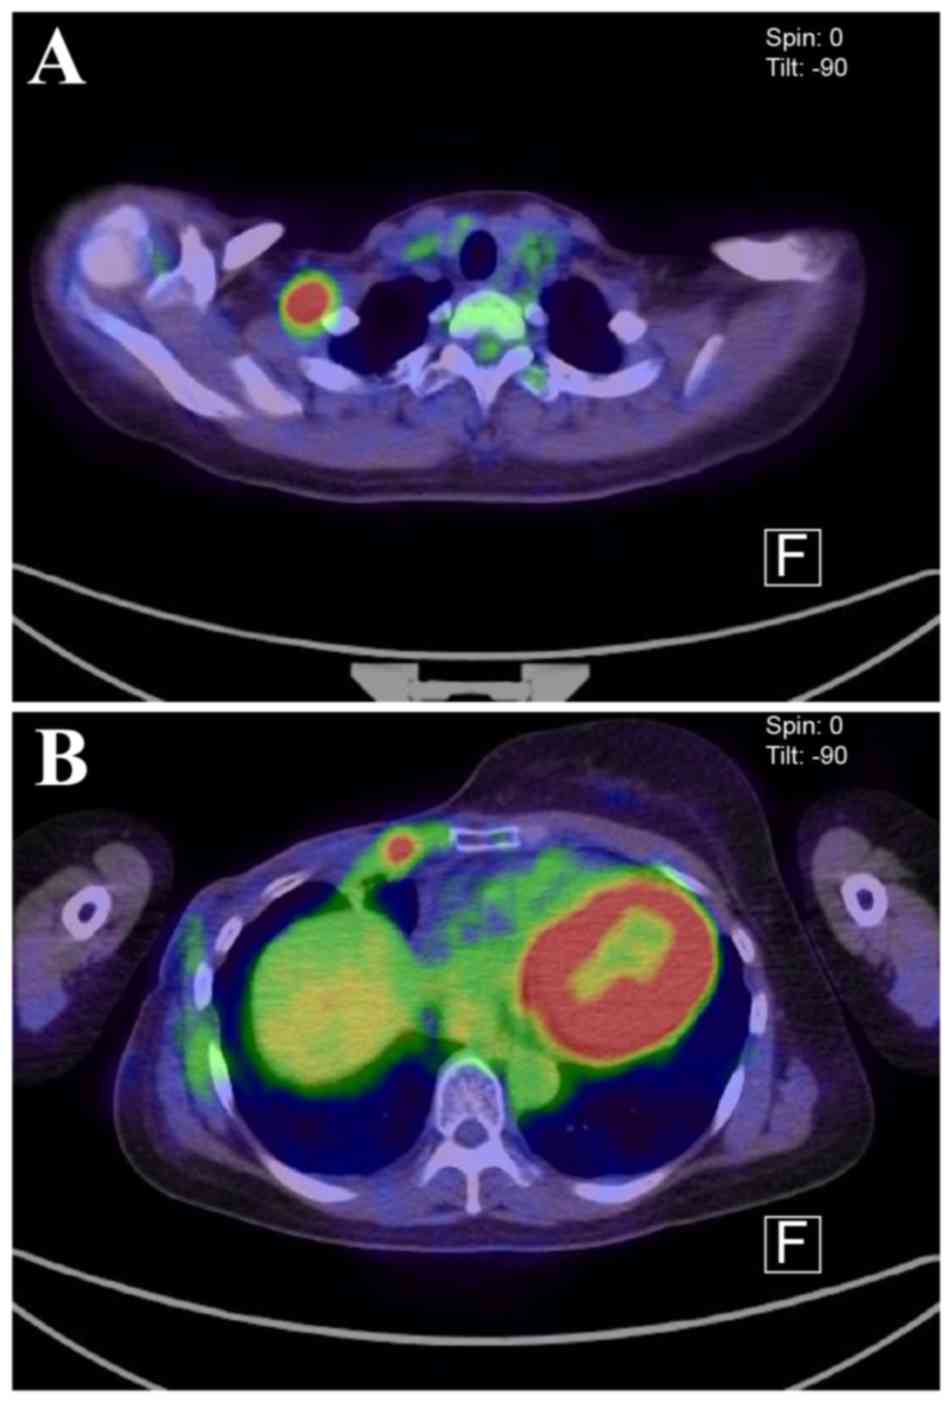

Pathological examination revealed squamous cell carcinoma negative for estrogen receptor, progesterone receptor and human epidermal growth factor receptor 2 (Fig. 2). Six cycles of postoperative adjuvant chemotherapy with cyclophosphamide 500 mg/m2, epirubicin 75 mg/m2 and fluorouracil 500 mg/m2 (CEF regimen) were administered, following which an increase in the size of the ipsilateral sternal lymph nodes was observed. No other metastatic lesions were found on computed tomography (CT) scans, and the patient was subjected to lymphadenectomy with pleural drainage. Pathological examination of the resected nodes demonstrated metastatic squamous cell carcinoma. Docetaxel (75 mg/m2) was administered as adjuvant therapy; however, allergic symptoms developed, including respiratory distress and palpitations, and docetaxel was discontinued. Radiotherapy to the right thoracic wall and the right supraclavicular lymph node (60 Gy) was next administered. However, enlargement of the ipsilateral supraclavicular lymph node was observed 3 months after radiotherapy. Lymphadenopathy (lymph node enlarged to 2 cm in diameter) was identified on ultrasound examination, and fine-needle aspiration cytology confirmed the presence of metastatic squamous cell carcinoma. Fluorodeoxyglucose positron emission tomography (FDG-PET)-CT revealed accumulation in the anterior thoracic wall close to the previous surgical site (Fig. 3). Consequently, eribulin (1.4 mg/m2) was administered as initial therapy. The lymph node was not palpable at 1 month after therapy initiation, and at 3 months after chemotherapy the enlargement had completely disappeared, as demonstrated on a CT examination. No metastatic lymph node or thoracic wall FDG accumulation was observed on PET-CT 11 months after treatment initiation (Fig. 4). After 17 months of treatment, the patient remained metastasis-free. During those 17 months, no major side effects were observed although peripheral neuropathy not affecting daily life grade 1 peripheral neurotoxicity occurred.

Figure 4.

Positron emission tomography-computed tomography scan at 11 months after the initiation of chemotherapy confirmed the disappearance of FDG accumulation at (A) supraclavicular lymph node and (B) anterior thorax of previous surgical site.